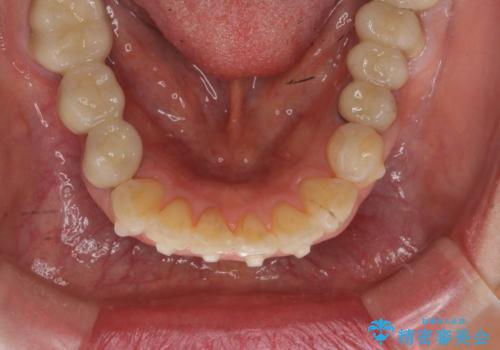

前歯の突き上げを改善する インビザライン による小矯正

- 下顎前歯のガタつきにより上顎前歯のクラウンに突き上げ・動揺が認められ、また歯ぎしりもあることから下顎前歯のみの小矯正をインビザライン で行うこととなりました。

このおようなリスクを最大限回避するためにも、咬合調整や小矯正により大きな力が上顎前歯にかからないような環境を整えることが大切です。